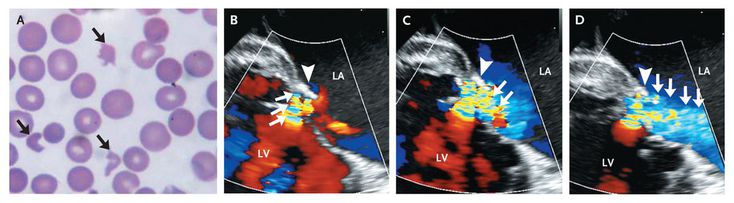

An 80-year-old woman with a history of mitral-valve repair presented with fatigue. On examination, she had normal vital signs and markedly pale conjunctivae. A grade 3/6 pansystolic murmur was audible at the apex, with radiation to the back. The hemoglobin level was 8 g per deciliter. Hematologic studies revealed indirect hyperbilirubinemia (total bilirubin level, 5.1 mg per deciliter [87 μmol per liter]), a lactate dehydrogenase level of 8320 U per liter, and a negative Coombs' test. A peripheral-blood smear showed schistocytes (Panel A, arrows), spherocytes, and polychromasia suggestive of hemolytic anemia. Transesophageal echocardiography showed a jet of mild transvalvular mitral regurgitation (Panels B, C, and D, arrows; see the video) that immediately collided with the annuloplasty ring (Panels B, C, and D, arrowhead), redirecting the jet in an acute angle into the left atrium (Panel D, arrows). LA denotes left atrium, and LV left ventricle. Residual mitral regurgitation, even if mild, can result in erythrocyte fragmentation. The patient underwent mitral-valve replacement, which resulted in resolution of the hemolysis.